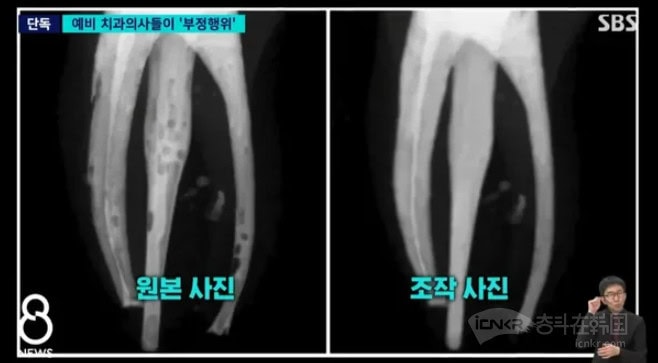

2025 年第二學期神經治療實習課程中,約 40 至 50 名學生因操作不熟練,導致根管填充出現多處空隙及氣泡、填充物分佈不均,甚至部分根管完全未有填充。這些缺陷在 X 光片上清晰可見,是評估根管治療質素關鍵依據。 學生利用 Photoshop 等修圖軟件修補照片,提交呈現無氣泡、無空隙假象 X 光片,部分學生甚至直接下載網上完美案例 X 光片替換自己失敗作品。

教授發現照片過於完美揭發造假

一名細心教授批改實習報告時,發現多名學生 X 光片過於完美,且存在相似修圖痕跡。他隨即調取原始診療記錄及實時監控錄影,發現學生實際操作與提交 X 光片嚴重不符。校方成立專項調查組,對全部約 80 名參與課程學生 X 光片進行技術鑑定,揭發這次集體造假事件。